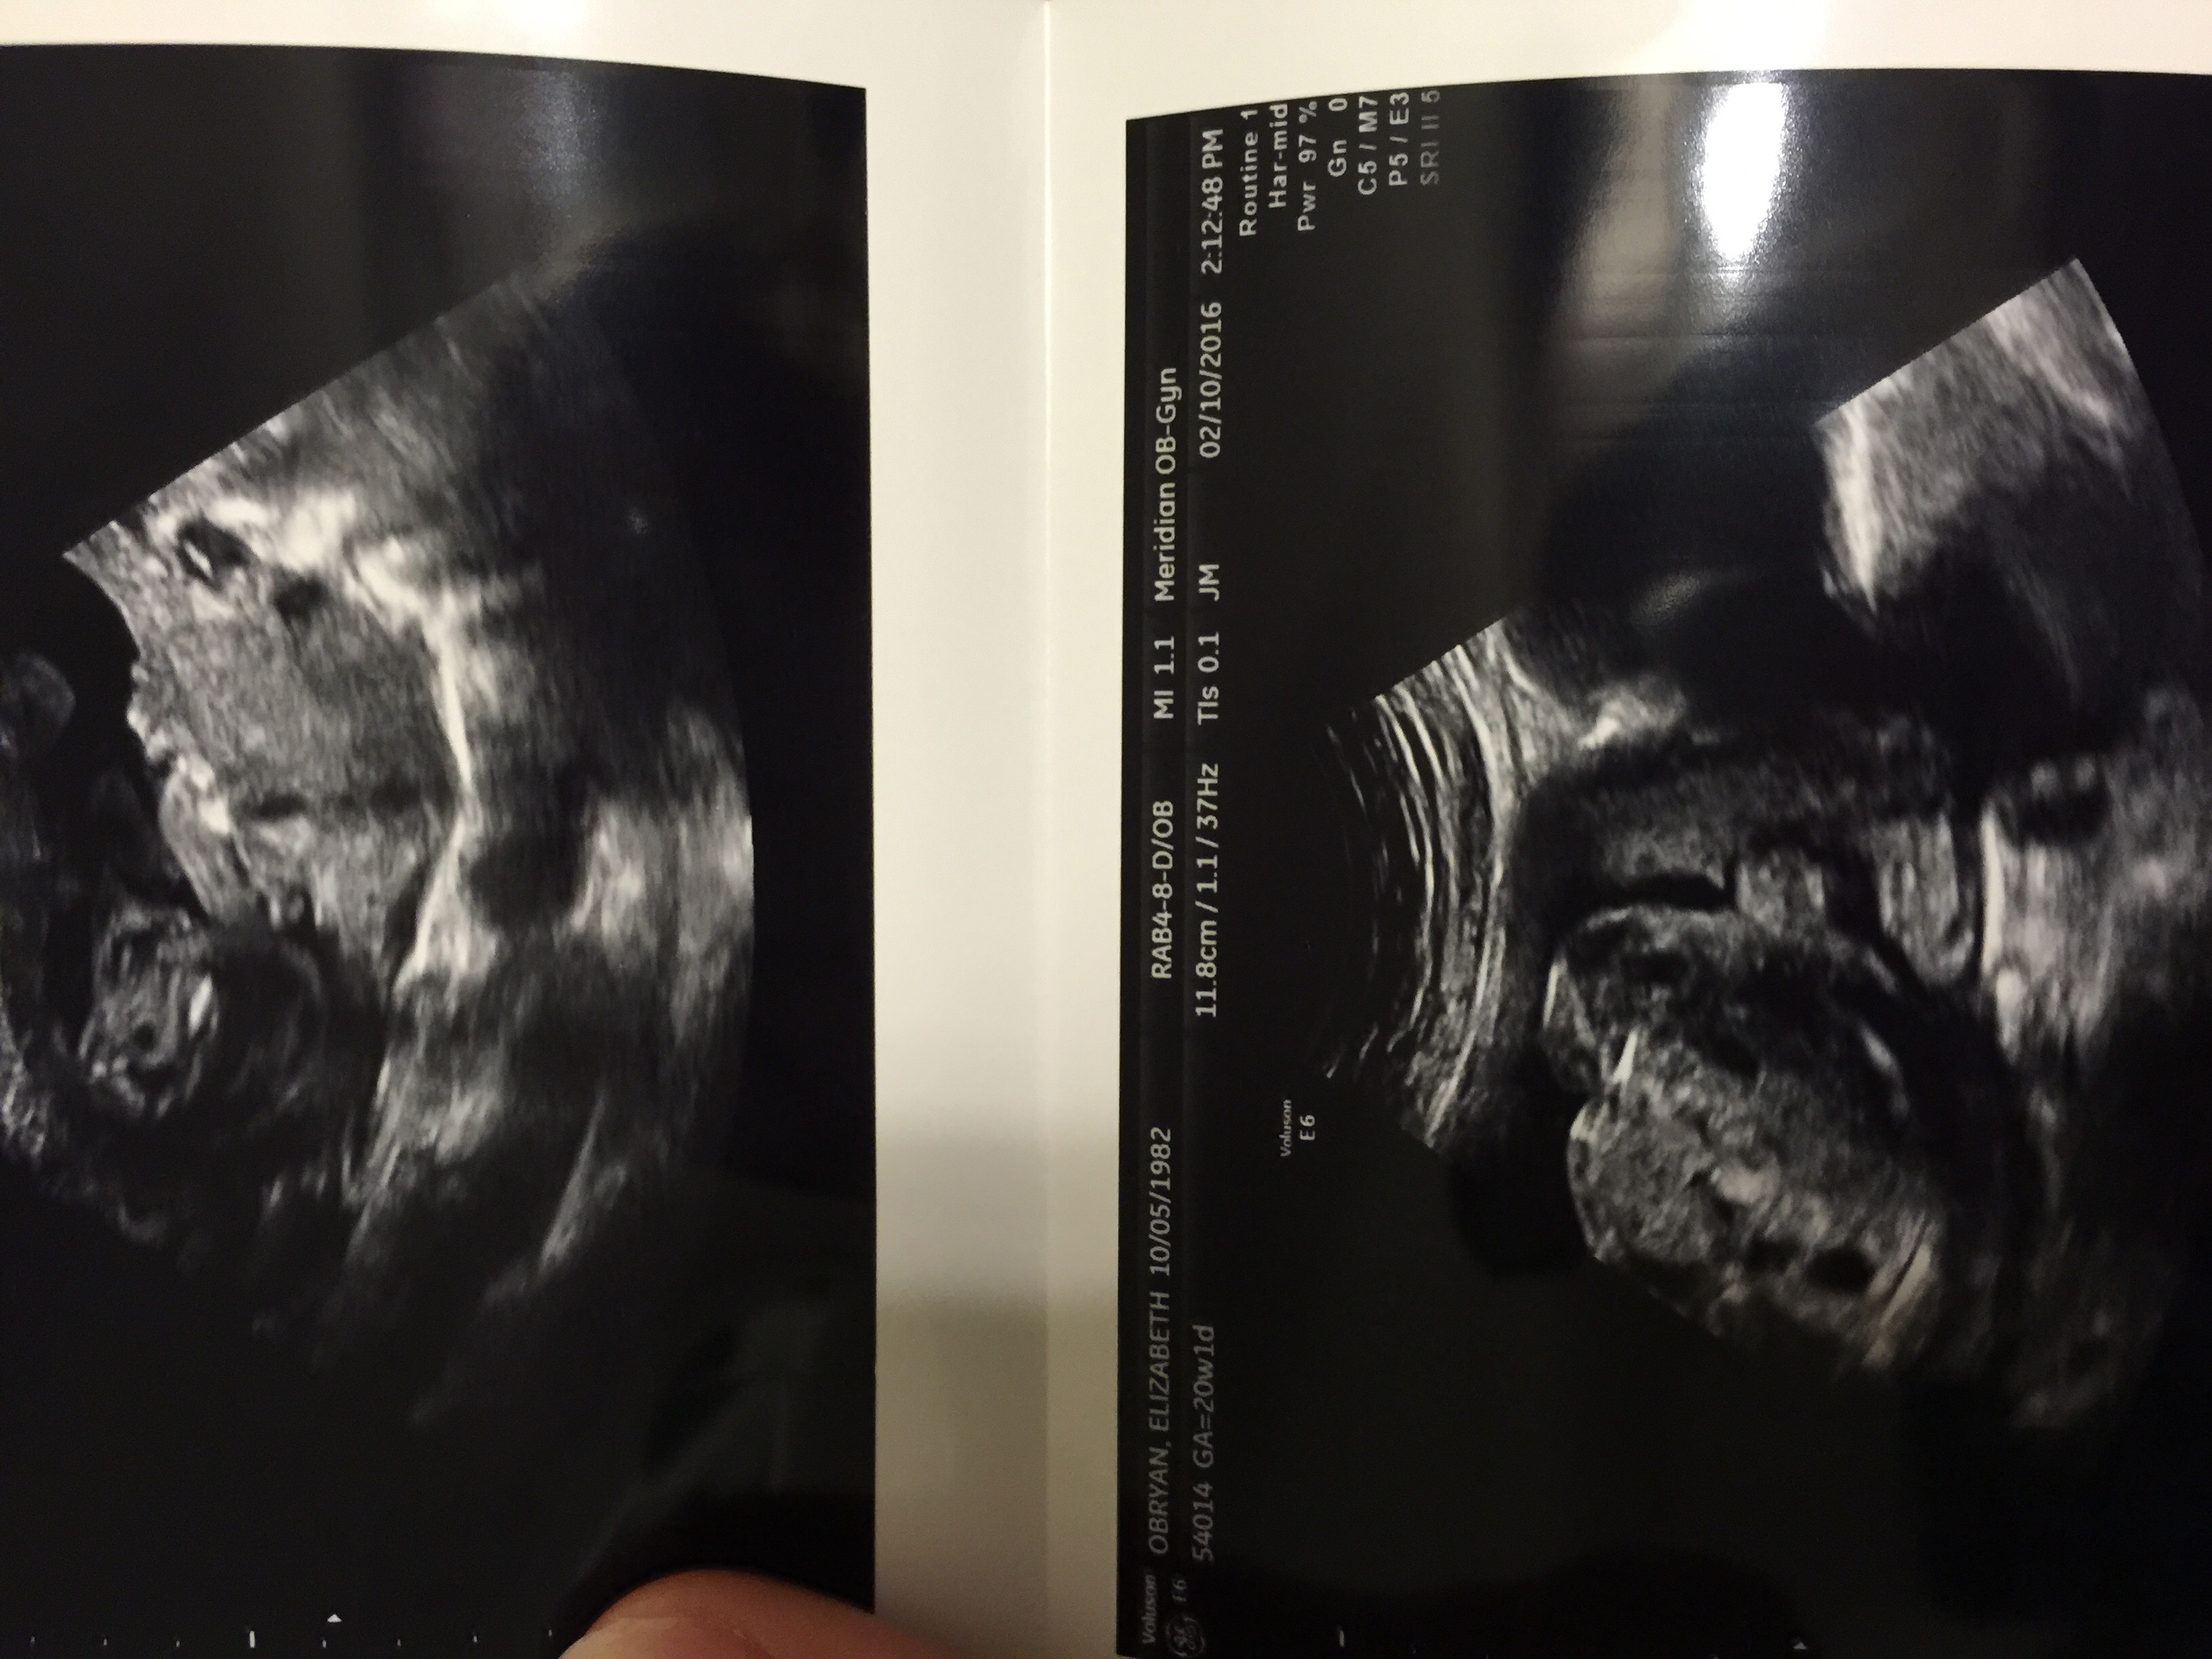

20 weeks ...what do you think??Attachment 29827

1st pic i think boy, cant see any clues on 2nd x

Sorry it might just be me but I'm having trouble working out what I'm actually looking at x

It's not just you mamma. I have no idea either. Are you sure these are potty shots lol

I can't see anything looking like a potty shot here, sorry. What did the tech say? Do you have any 12-14 week nub (full body profile) shots?

Nope she put these in an envelope and sealed it saying these are the potty shots

I only had one initial at 8 weeks and then my 20 week. My husband didn't want to know so asked her to put potty shots in an envelope so I could guesses and that's what she gave me. Darn....